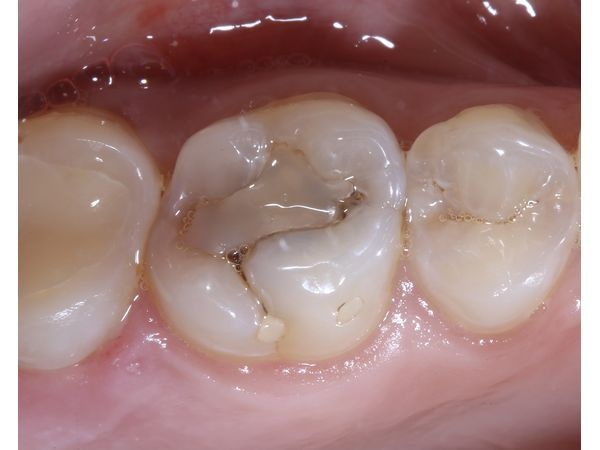

- несостоятельную пломбу с нарушением краевого прилегания и рецидивом кариеса в зубе 1.6.

КТ верхней и нижней челюсти показала тень глубокой кариозной полости под несостоятельной пломбой в правом верхнем моляре.